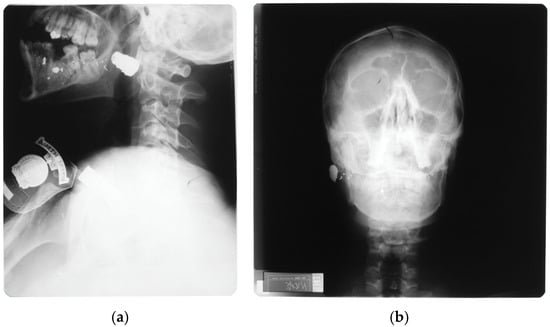

- Failla, A.V.M.; Licciardello, G.; Cocimano, G.; Di Mauro, L.; Chisari, M.; Sessa, F.; Salerno, M.; Esposito, M. Diagnostic challenges in uncommon firearm injury cases: A multidisciplinary approach. Diagnostics 2025, 15, 31. [Google Scholar] [CrossRef]

- Cooper, P.R. Gunshot wounds to the brain. In Head Injury, 3rd ed.; Cooper, P.R., Ed.; Williams & Wilkins: Baltimore, MD, USA, 1993; pp. 355–371. ISBN 0-683-02108-7. [Google Scholar]

- Aarabi, B.; Eisenberg, H. Surgical management and prognosis of penetrating brain injury. In Youmans & Winn Neurological Surgery, 8th ed.; Winn, H.R., Ed.; Elsevier: Philadelphia, PA, USA, 2023; pp. 3092–3104. ISBN 978-0-323-66192-8. [Google Scholar]

- Part2: Prognosis in penetrating brain injury (no authors listed). J. Trauma 2001, 51 (Suppl. S2), S44–S86.

- Rosenfeld, J.V.; Bell, R.S.; Armonda, R. Current concepts in penetrating and blast injury to the central nervous system. World J. Surg. 2015, 39, 1352–1362. [Google Scholar] [CrossRef]